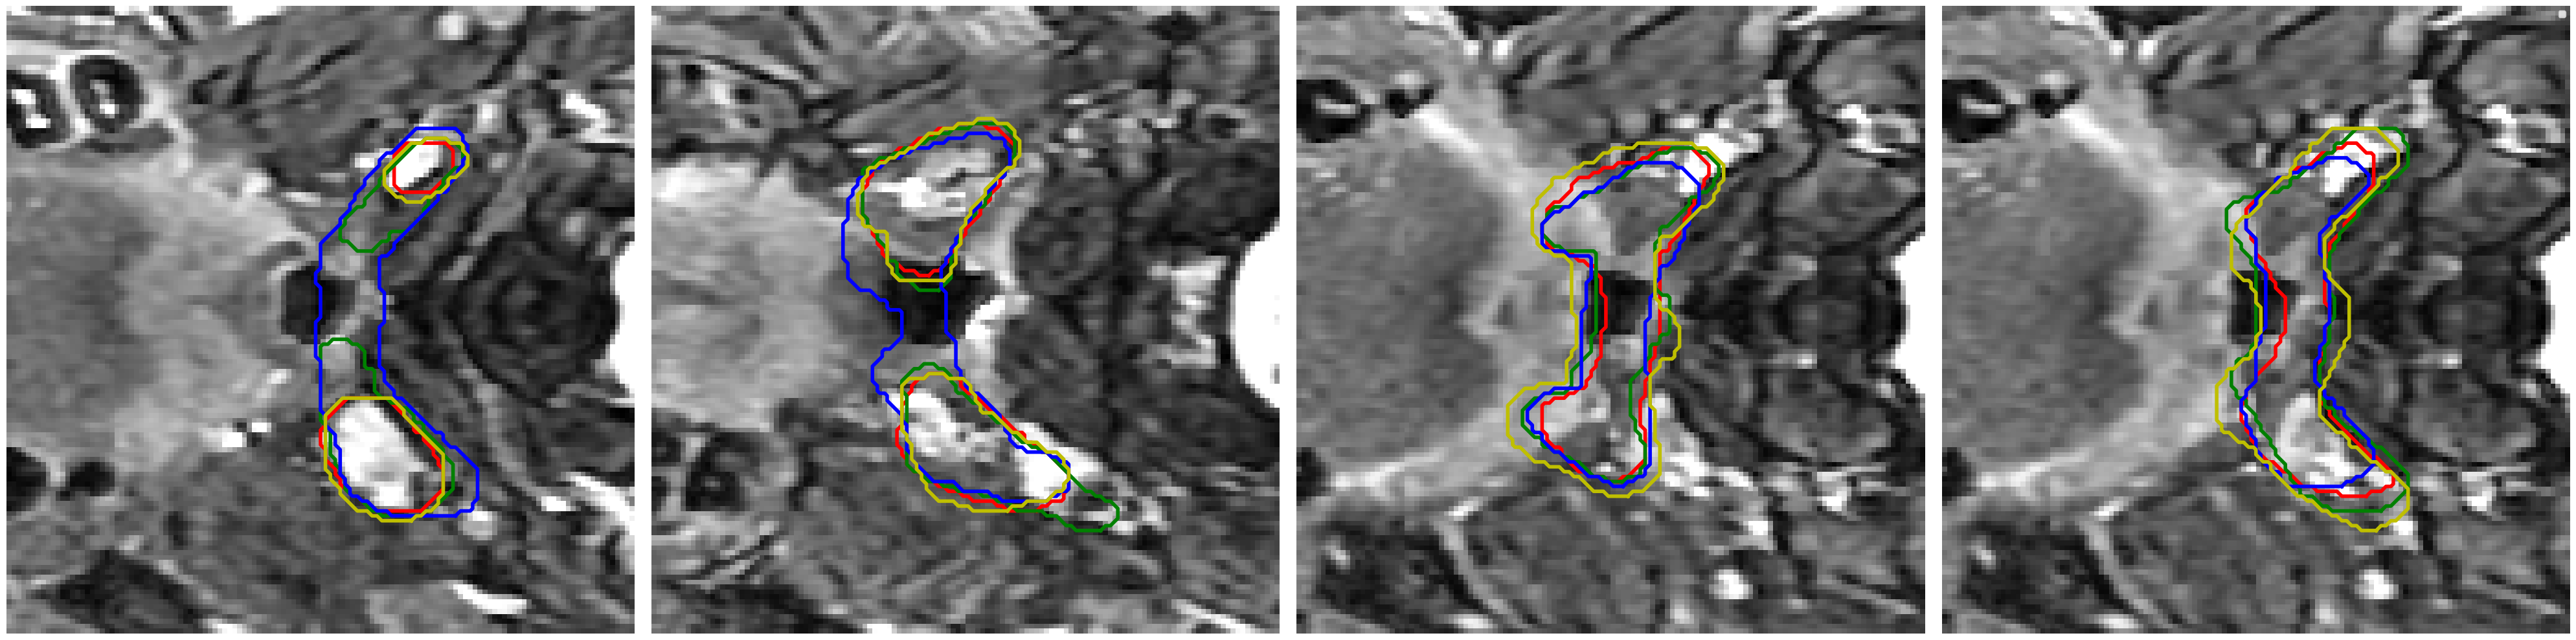

Visual comparison of segmentation results.

We provide visual comparisons of the segmentation results of all methods on the NPC dataset in Fig. 9 and Fig. 10, where different colors indicate the segmentation is obtained by different expert annotators. The segmentation results of ProSeg are more diverse and personalized than those of other methods. The segmentation results of ProSeg are more consistent with the ground truth while maintaining diversity among the generated segmentations. The results demonstrate that ProSeg effectively captures expert-specific characteristics and generates diverse segmentation results. For some methods, the segmentation from all the experts is the same, which means the diversity is poor. In Fig. 6(b), the second row shows the segmentation from our ProSeg, the third row shows the segmentation from the DPersona (stage 1) and the fourth row shows the segmentation from the DPersona (stage 2). For the second image, in the gold standard, three experts give segmentation containing two separate parts. Our ProSeg captures the character, while other models can hardly capture this difference, and generation methods can not tell which expert gives the two-part segmentation as shown in the figure that the color of the two-part segmentation is different from the Gold standard.